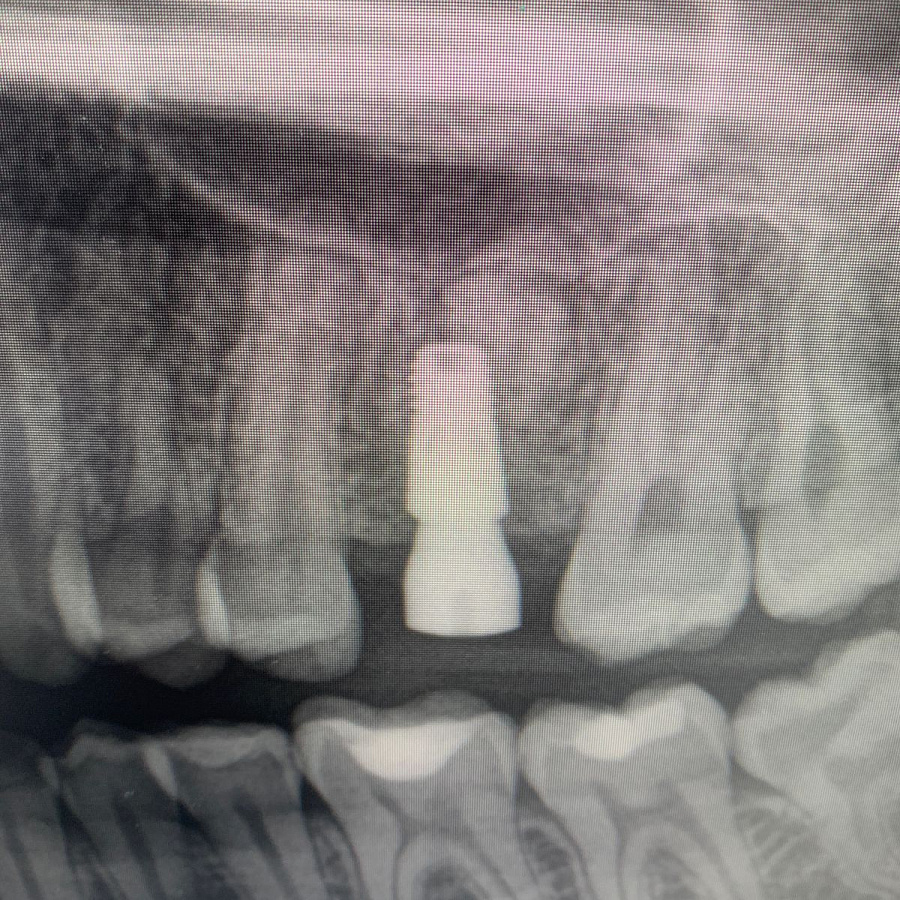

Через 6 месяцев после подсадки кости - контрольный снимок и установка зубного имплантата.

Спустя 6 месяцев пациент готов к протезированию.